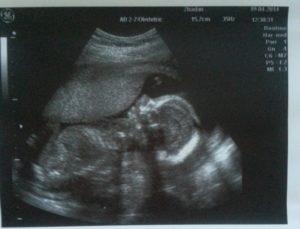

Для диагностики гипертонуса используется ультразвуковое исследование, при проведении которого может быть выявлен гипертонус задней стенки матки, а также передней. Однако, этот признак не всегда может говорить об угрозе прерывание беременности. Матка может прийти в тонус в ответ на прохождение ультразвуковой волны через ее стенку.

Также на ультразвуковом исследовании при выполнении цервикометрии (измерение длины шейки матки) диагностируется истмико-цервикальная недостаточность (укорочение шейки матки, открытие ее внутреннего зева).

Определить локальный гипертонус матки по задней или передней стенке можно с помощью ультразвукового исследования. При этом на УЗИ видно изменение стенки матки в месте её тонуса, она прогибается вовнутрь.